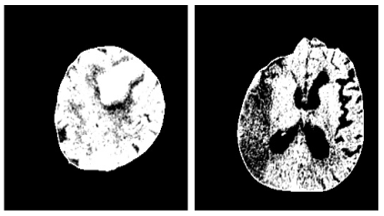

Figure 6 depicts the image samples from the dataset for Hemorrhagic and Ischemic Brain Stroke. In Figure 6, the left side image represents the Hemorrhagic stroke brain image and right-side image represents the Ischemic Brain Stroke. Figure 7 depicts the results after thresholding process and Figure 8 depicts the results after normalization. Performance metrics like recall, precision, f1-score, loss and accuracy are considered to evaluate the proposed model. The performance obtained by the proposed model for 10 trials is presented in Table 3.

Figure 7. Images after thresholding

Figure 8. Images after normalization